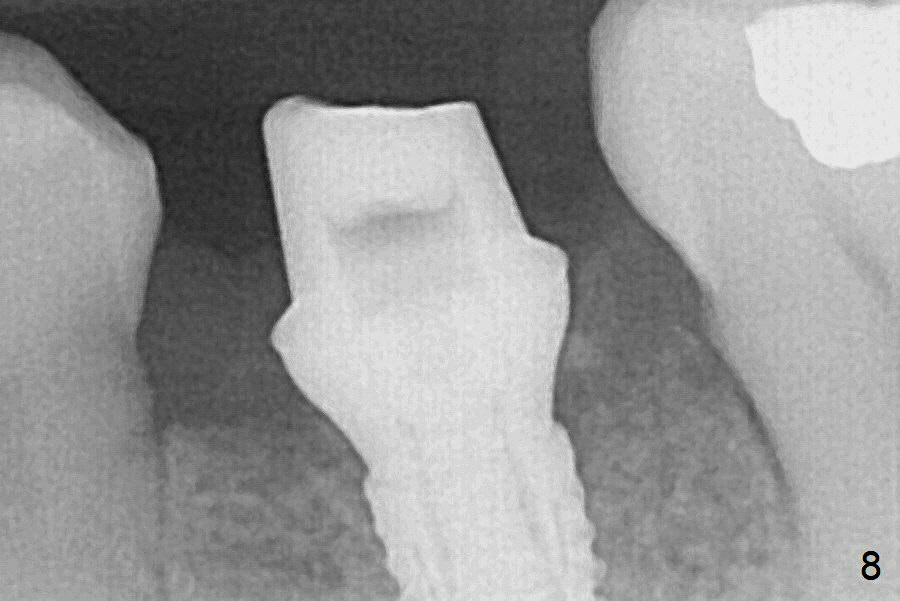

Extraction of the lower left 2nd premolar with vertical fracture (Fig.1,2 >) is easy because of peri-radicular radiolucency. The apical end of the osteotomy is not shown with a 2 mm pilot drill (Fig.3) or a 3.8x18 mm implant (Fig.4) in place. It appears that the implant is not placed deep enough. Following 3-4 more turns of the implant and placement of a 5.5x4(3) mm abutment (Fig.5 A), allograft is placed (*). A postop panoramic X-ray is taken (Fig.6); the osteotomy could have been deepened to reduce the possibility of periimplantitis. Retrospectively, the panoramic X-ray should be taken after use of the pilot drill. The bone around the implant appears to have regenerated 4 months postop (Fig.7,8). Bone density appears to continue increasing 9 months postop (i.e., 4.5 months post cementation, Fig.9). Bone loss is minimal 2 years post cementation (Fig.10).